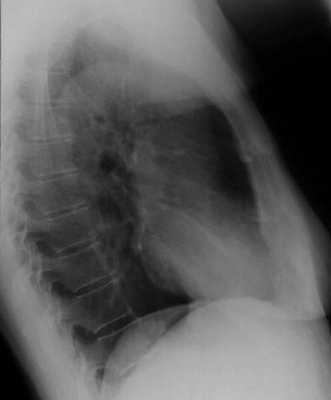

Рентгенография бывает обзорной и прицельной. Обзорные снимки, как правило, должны выполняться в двух проекциях - прямой и боковой (исследуемой стороной к кассете). На обзорных рентгенограммах грудной клетки всегда будут видны как передние, так и задние отделы ребер, ключица, лопатка, позвоночник и грудина, независимо от проекции снимка (рис. 3.1 и 3.2). Этим отличается обзорная рентгенограмма от томограммы.

Рис. 3.2. Обзорная рентгенограмма легких в правой боковой проекции. Норма (см. текст).